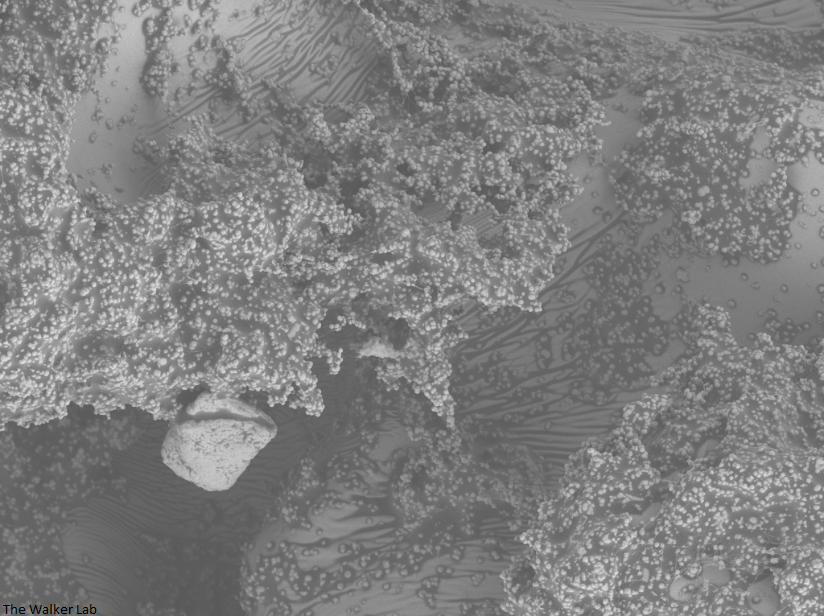

SEM Images of Mouse Catheters

Silicone urinary catheters have smooth surfaces, while latex urinary catheter surfaces are rough. Regardless of the catheter material, deposition of host inflammatory factors alters the surface and facilitates infection by atypical pathogens.

Urinary catheters render people susceptible to atypical uropathogens. We use the atypical uropathogen, methicillin-resistant Staphylococcus aureus (MRSA), to study the catheter-host-pathogen interactions that facilitate disease.

The host inflammation response to the catheter recruits immune cells and wound healing proteins which are deposited on the catheter surface. Atypical pathogens can use these host factors to adhere to the catheter's large surface and create biofilm. Colonization of catheters occurs quicker than expected and develops even in the presence of prophylactic antibiotic therapy. MRSA is just one of the uropathogens that can attach to the altered urinary catheter surface. One host factor deposited on the catheter surface is fibrinogen. We recently discovered that MRSA binds fibrinogen to attach to the catheter surface and form biofilm, which increases antibiotic recalcitrance. Our future studies aim to develop new non-antibiotic strategies that interfere with those interactions to prevent or treat CAUTIs.